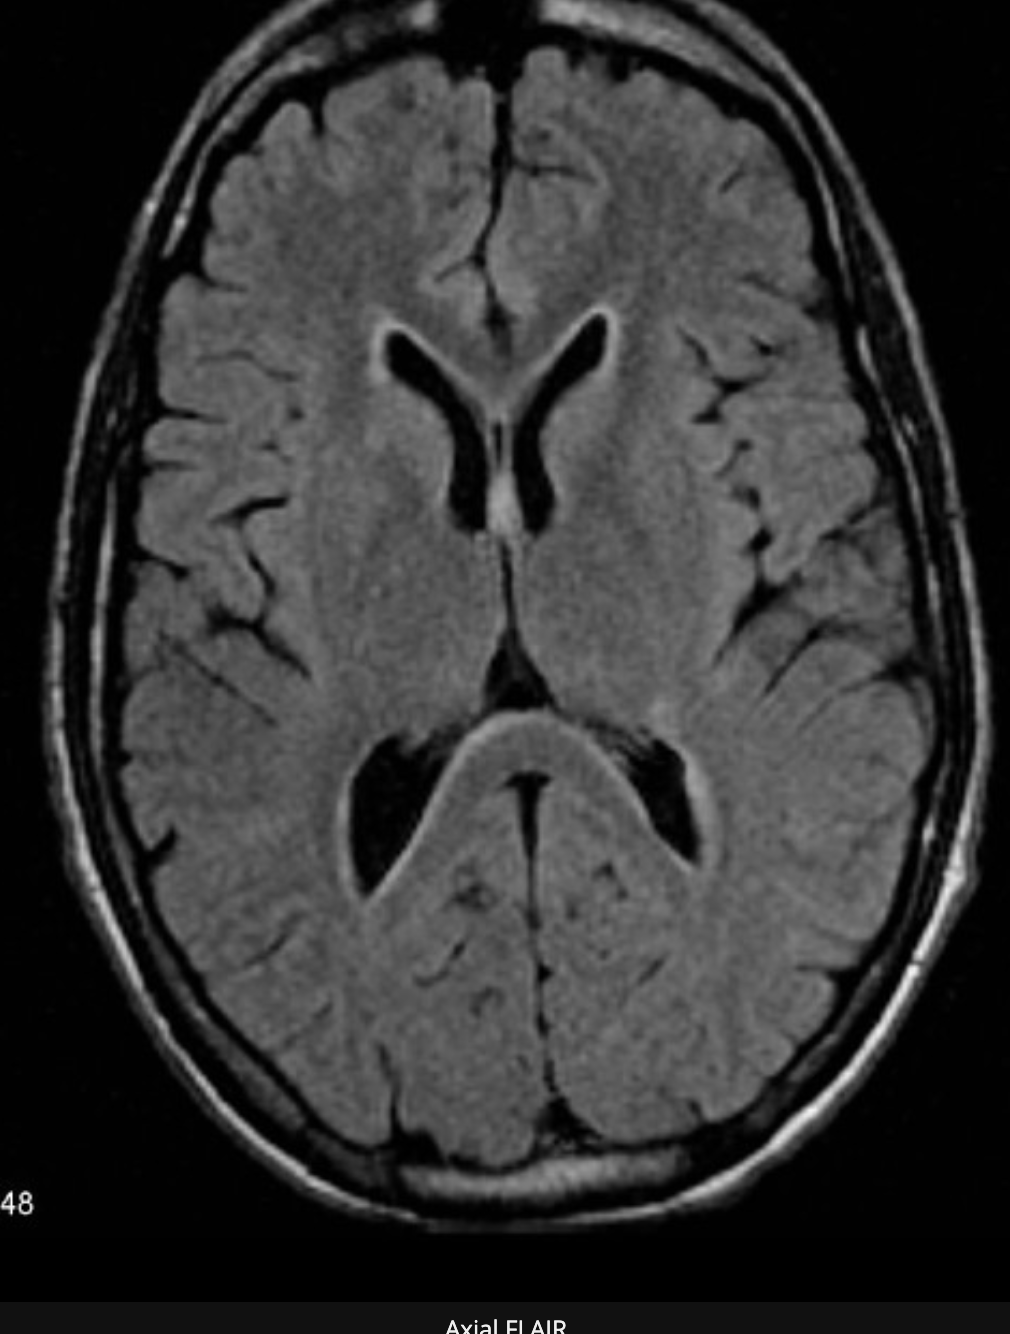

Corticobasal Degeneration (CBD)

CBD is a rare entity which may present with cognitive dysfunction, usually in combination with Parkinson-like symptoms.

The so-called ‘Alien-hand’ syndrome is a typical manifestation.

MRI shows asymmetric parietal cortical atrophy, sometimes with associated hyperintensity of the white matter on T2W images.

Axial FLAIR image shows striking asymmetric cortical parietal atrophy in a patient with CBD